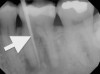

Chronic apical abscess is typically indicated by a radiograph that reveals a radiolucency. Clinically, there is a sinus tract present on the gingival tissue. It is paramount that the draining sinus tract be traced with a gutta-percha cone and then radiographed (Figure 3 and Figure 4).

Clinical confirmation of the periradicular diagnosis—chronic apical abscess on tooth No. 19. The tooth is not sensitive to percussion or palpation. A gutta-percha #25/.04 cone is inserted into the sinus tract.

Figure 3